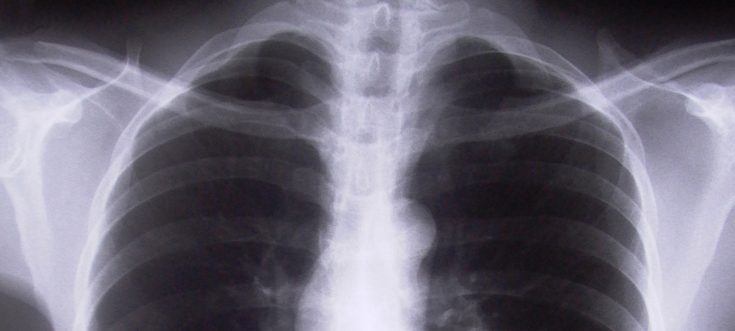

Ένα πρωτοφανές περιστατικό που σημειώθηκε στην Τήνο έρχεται στο φως της δημοσιότητας. Ένας πολίτης που ήθελε να υποβληθεί σε μια ακτινογραφία θώρακος, απευθύνθηκε σε.. κτηνίατρο, λόγω ελλείψεων στο Κέντρο Υγείας.

Σύμφωνα μάλιστα με τον γιατρό, δεν είναι η πρώτη φορά που κάτοικοι του νησιού χρειάζεται να βγάλουν ακτινογραφία, αλλά αυτό δεν είναι εφικτό λόγω βλάβης. “Γνωστοί μου είχαν περάσει Covid στο νησί και τους είχε μείνει ένας υπολειμματικός βήχας. Ποτέ δεν μπόρεσαν να έχουνε μία ακτινογραφία θώρακος”, αναφέρει ο κτηνίατρος.

“Δυστυχώς πρέπει να πάει σε άλλο νησί, είτε στη Μύκονο είτε στη Σύρο που καταλαβαίνετε ότι αυτό είναι μεγάλο πρόβλημα γιατί μπορεί να είναι ένας άνθρωπος ο οποίος έχει μία πνευμονία” προσθέτει η κ. Παπαδοπούλου.